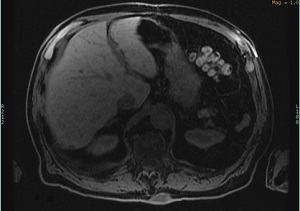

Figure 1. DISCO liver image